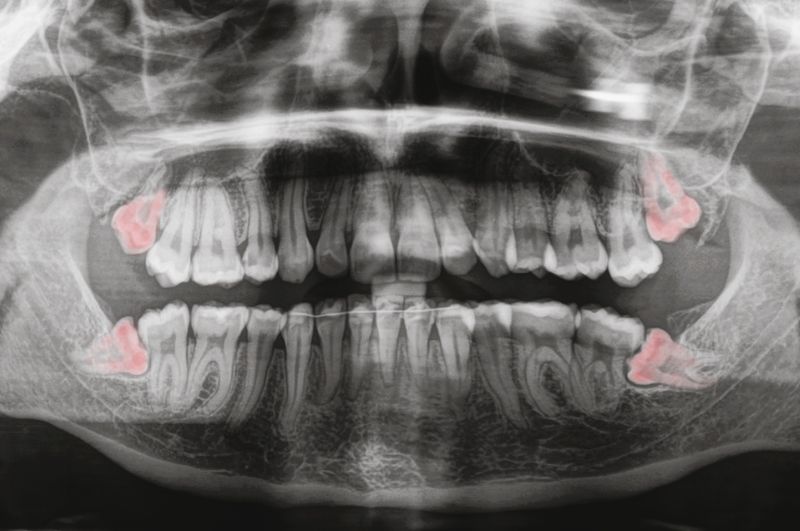

Jak wygląda chirurgiczne usuwanie ósemek?

Chirurgiczne usuwanie ósemek, zwanych zębami mądrości, to zabieg z zakresu chirurgii stomatologicznej, który wykonuje się w gabinecie stomatologicznym. Zabieg zazwyczaj przeprowadza się przed rozpoczęciem leczenia ortodontycznego, w przypadkach kiedy występuje zaawansowana próchnica, dolegliwości bólowe lub nieprawidłowe położenie zęba w łuku.